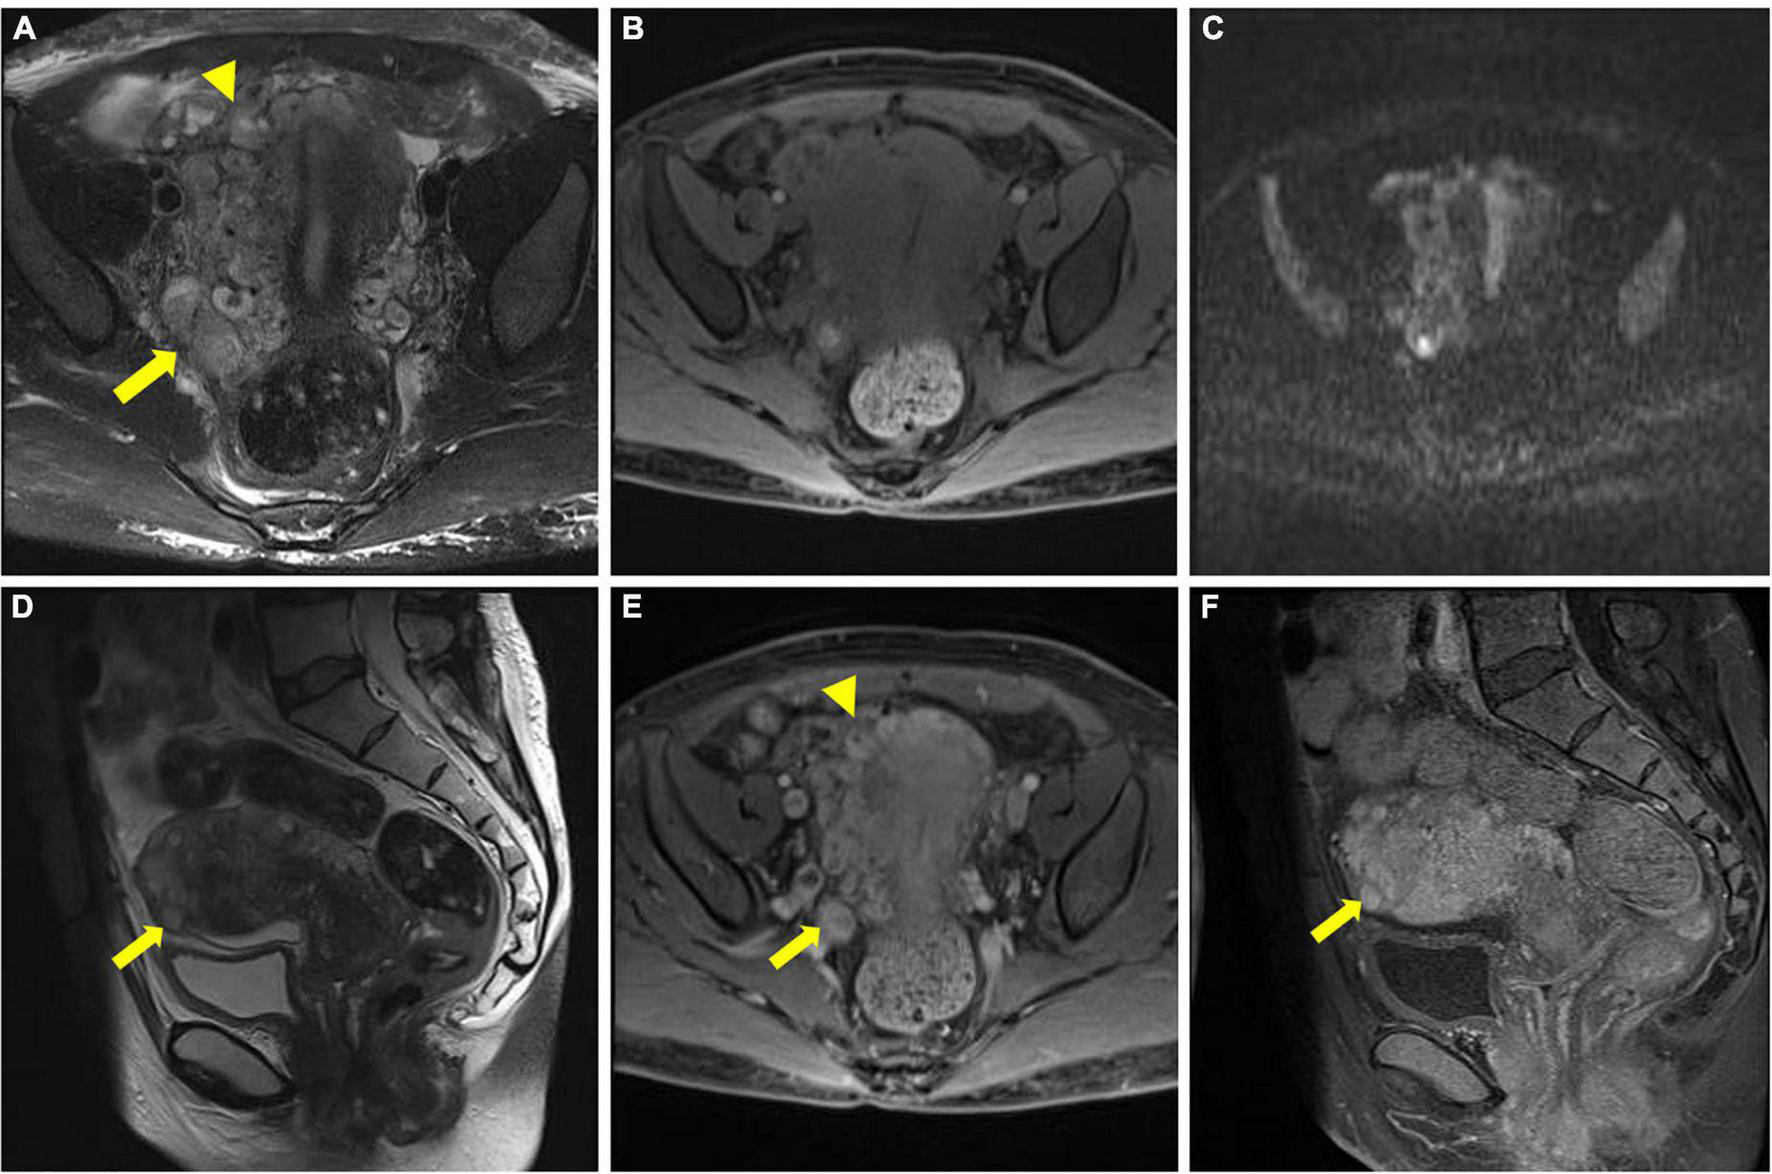

FIGURE 3

Pelvic magnetic resonance imaging (MRI) image. (A–C) Multiple tortuous and dilated vascular structures at the fundus of the uterus (arrowhead) and the parametrium (arrow). (D) Multiple nodules of varying sizes were observed at the fundus of the uterus (arrow). (E,F) After gadolinium-based contrast material injection, progressively enhanced lesions were noted within the lumen (arrowhead and arrow in E), and the nodules also presented progressive enhancement (arrow in F).